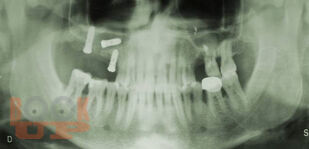

В учебном пособии рассматриваются вопросы клинико-рентгенологической диагностики хирургических осложнений дентальной имплантации, возникающие в интраоперационном и раннем послеоперационном периодах. Разделы пособия содержат клинические примеры осложнений, возникающих на хирургическом этапе имплантологического лечения больных. В отдельной главе, посвященной социологическому исследованию, приведены данные анкетирования врачей-стоматологов по проблемам имплантологического лечения, которые позволяют выявить наиболее острые проблемы, стоящие перед имплантологами, в том числе, пробелы в послевузовском образовании. Пособие иллюстрировано цветными фотографиями, облегчающими восприятие излагаемого материала.